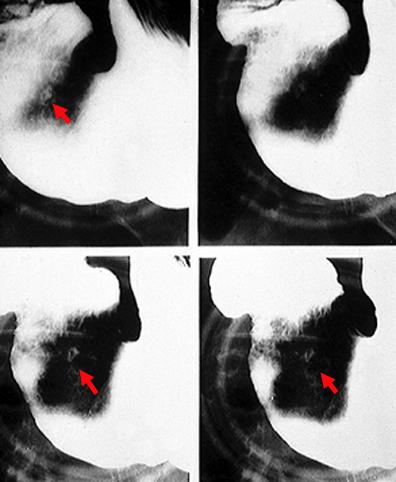

clasificación del pacienteTumor Epitelial Maligno/Adenocarcinoma

parte(separada por órganos)estómago(región)/mas de dos

método de exámenRayos X

clasificación ectoscópica de tumoresTipo 4(Tipo difusamente infiltrado)/

diámetro mayor del tumor40 -

grado de penetraciónss(a1)